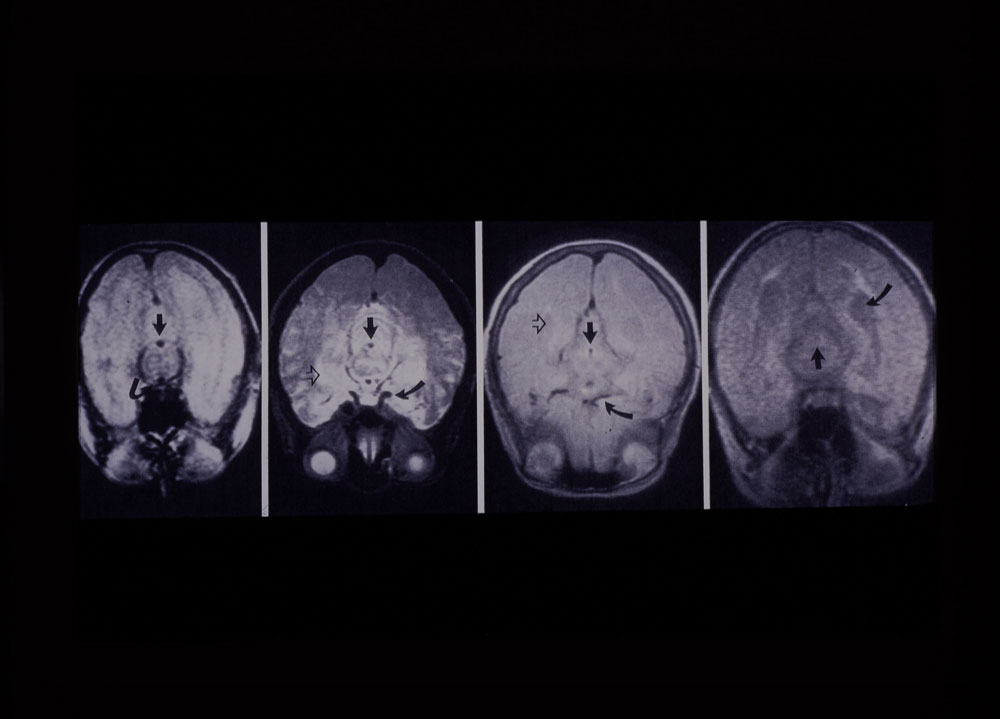

A classically trained physicist, Mansfield realised he could exploit the phenomenon of nuclear magnetic resonance (NMR) to create cross-sectional images of living tissue. He developed a safe and non-invasive technique to create images of soft tissue and organs in a 'slice' of the human body in spectacular detail, revolutionizing medical diagnosis and changing how the human brain is studied. His first paper on the topic of MRI was published in the Journal of Physics: C in November 1973.

This research was the start of the development of MRI that has since changed the face of modern medicine, enabling doctors to see detailed images of the interior of the living body without the potentially harmful effects of radiation or surgery. MRI can now detect in great detail the presence of cancer and signs of damage in the body’s bones, tissues and organs. Today, MRI scanners are used in hospitals all over the world and over 60 million investigations with MRI are carried out every year.